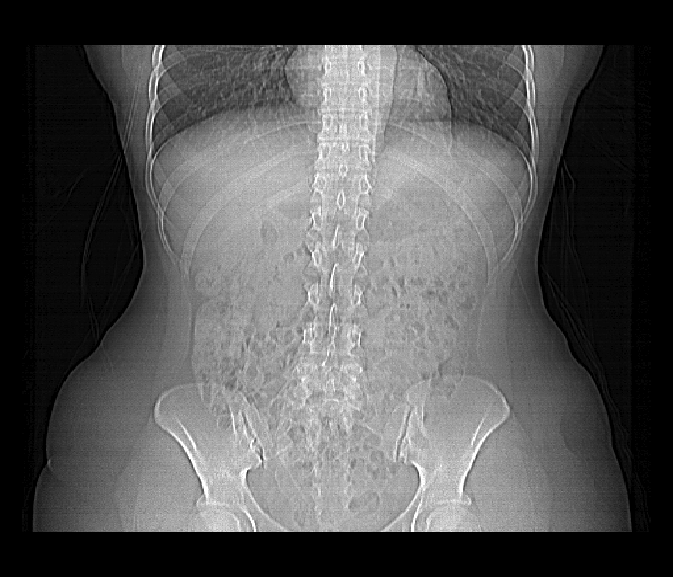

The first attempt at reading this file on line #2 fails. The error message is very informative, bytes 129-132 do not contain the characters DICM which is part of the DICOM Standard. So... it's safe to assume that this file is not a valid DICOM file. Delving further we turn on the debugging option (line #4) and are able to see what the first 128 bytes, which are skipped by default as part of the DICOM Standard, look like. They obviously contain information. By setting skipFirst128=FALSE and DICM=FALSE (line #13) we can override the default settings are start reading information from the first set of bytes. This does the trick and with the debugging option turned on every field from the header is displayed. No errors have occurred, so we can display the image data from this file (line #40) below.